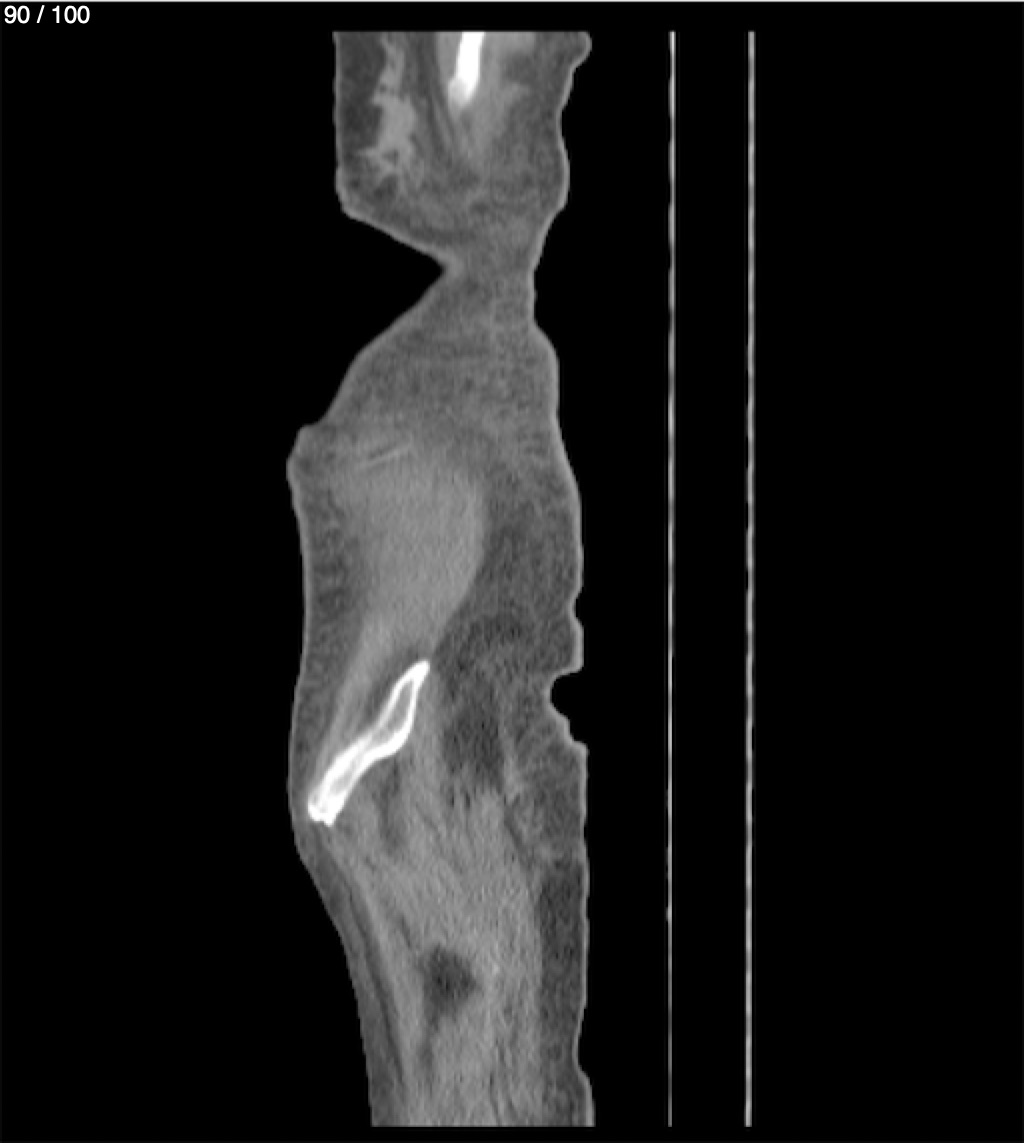

Hilda Geronimo Mendez 60A - T.C Abdomen Simple